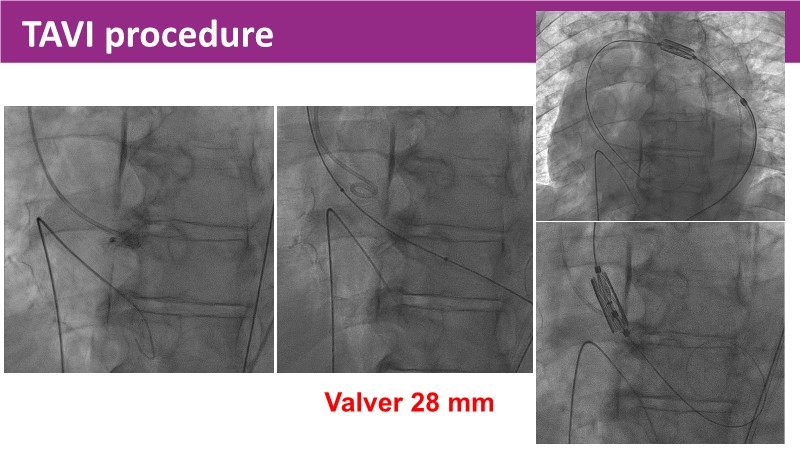

Discover the latest insights from the Myval THV series in this session from PCR London Valves 2025. Through real-world, case-based learning, the session explores lifetime management strategies for TAVI patients, the clinical relevance of intermediate and extra-large valve sizing, and the impact of foreshortening on accurate valve deployment.

Key presentations cover matching prostheses to patient anatomy, the importance of predictable valve performance in challenging situations, and pivotal trial data supporting Myval THV outcomes. Highlights include the OCTAPRO+ THV’s progressive design enabling precise deployment, the OctaAlign technique for commissural alignment, and next-generation strategies to optimize lifetime TAVI management.